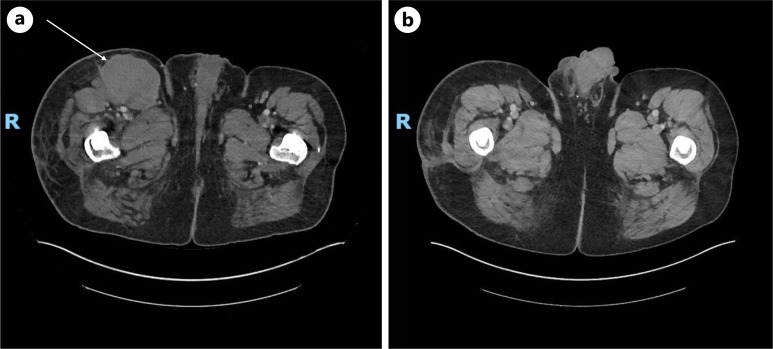

Case presentations: We describe two cases: first, HS in a 60-year-old man with primary tumor in the right anterior lower limb, and second, IDCS in an 82-year-old man in the right para-parotid region after initial wide local excision of a right postauricular mass suggestive of a pleomorphic undifferentiated sarcoma. Systemic imaging showed retroperitoneal, inguinal, and pelvic adenopathy in the first case and no distant metastases in the second case. Both were diagnosed via biopsy with extensive immunohistochemistry and were also found to be strongly positive on PDL1 testing. Treatment was initiated with ICIs in both patients, which was paired with palliative radiotherapy for the HS patient. Both cases exhibited a durable response to treatment upon repeated systemic imaging.